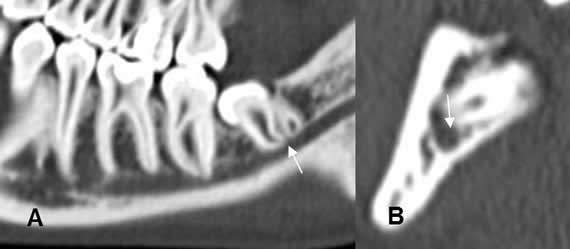

Fig 17. Canal mandibular.

A : TAC reconstrucción sagital y B: TAC reconstrucción transversal. Raíz de la pieza 38, en contacto con el canal mandibular, pero sin deformarlo.